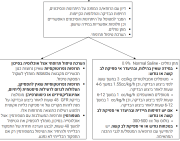

| 11:20, 22 באפריל 2024 | רפואה מגדרית1.png (קובץ) |  |

7 קילו־בייטים | Motyk | 1 | |